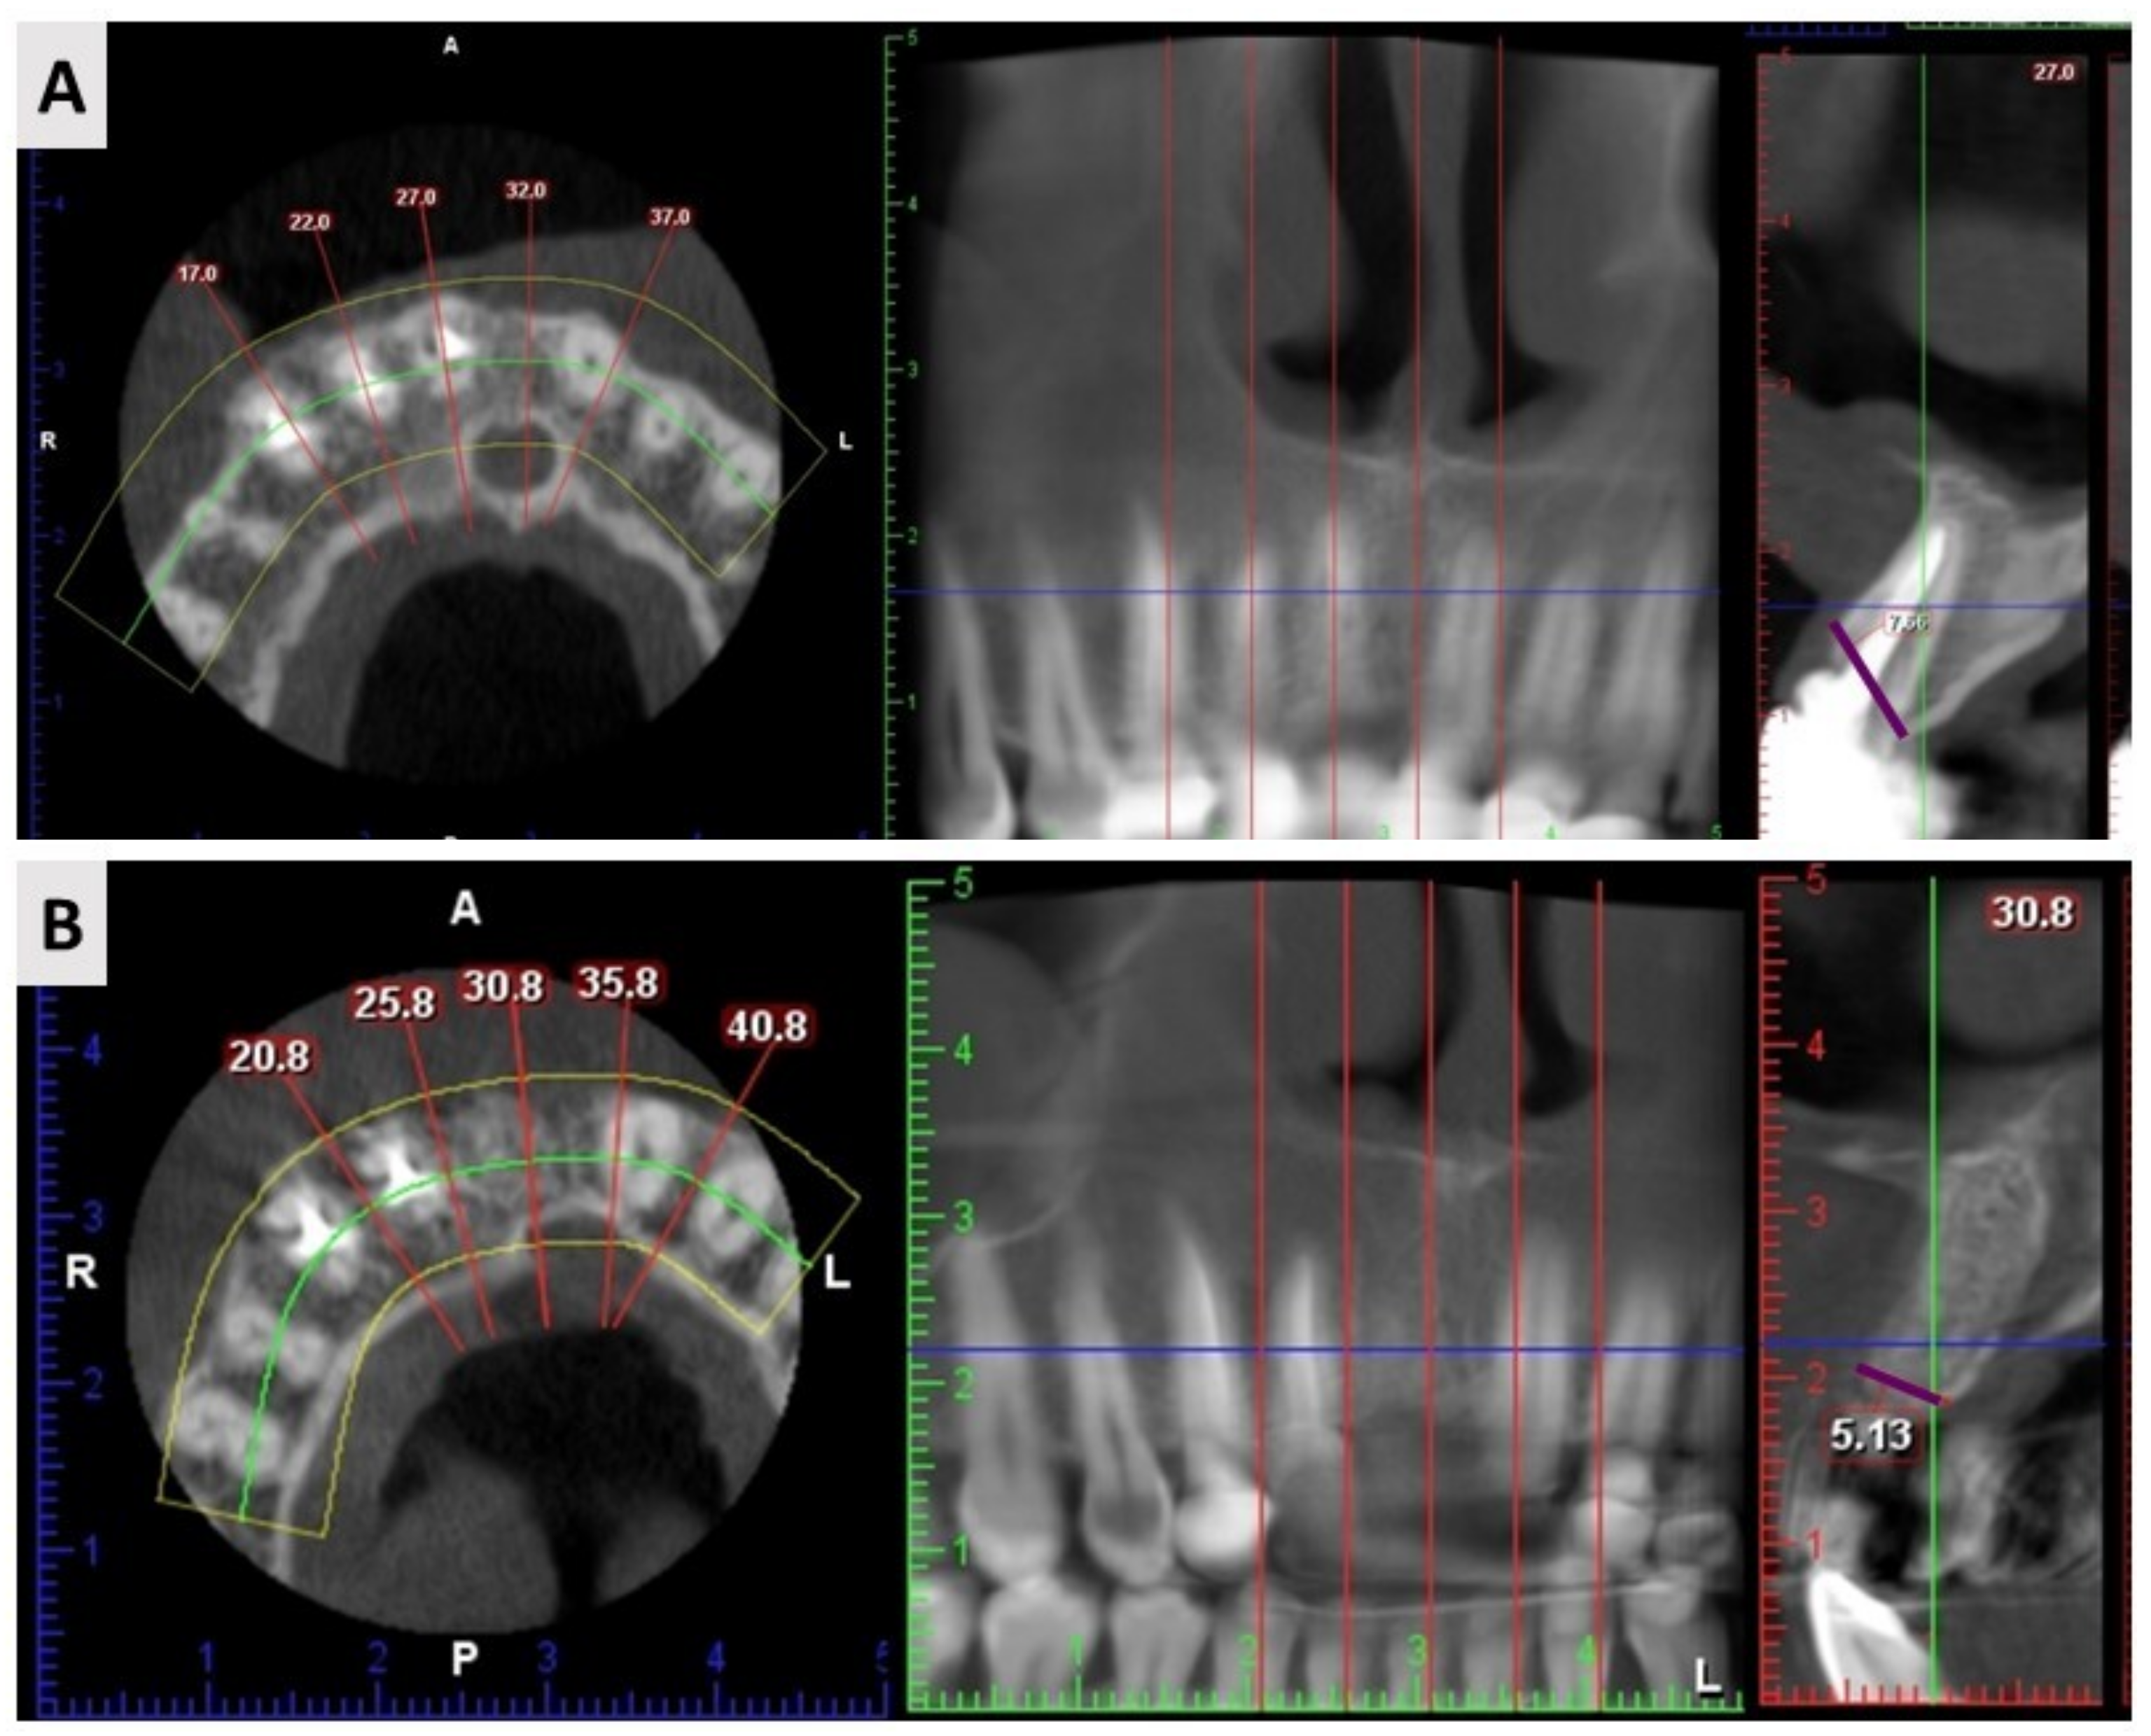

2.3. Cone Beam Computed Tomography (CBCT) Results

4.5. Radiological Assessment

| Width before Extraction | Width after Extraction | Net Change | |

|---|---|---|---|

| ADG 1 | 8.06 ± 1.34 mm | 7.18 ± 1.48 mm | −0.88 ± 0.76 |

| BX+AB 2 | 7.88 ± 1.08 mm | 6.64 ± 0.85 mm | −1.24 ± 0.99 |

| p-value * | 0.654 | 0.172 | 0.219 |